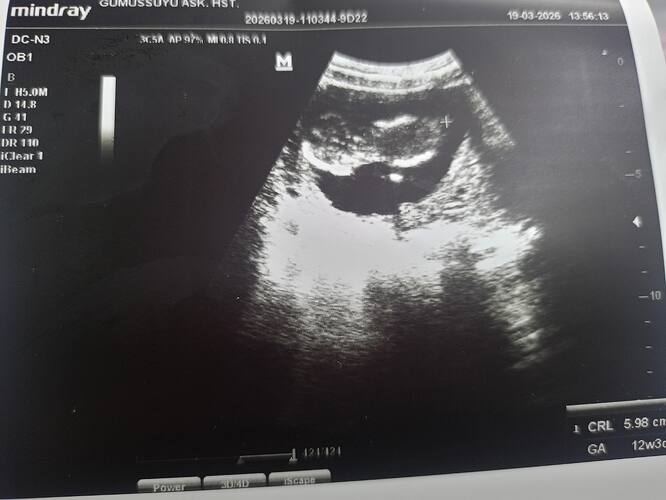

Kız bu erkege çok benziyor hakkında hayırlısı olsun sağlıkla kucağına almayı nasip etsin

bende çok erkek hissediyorum